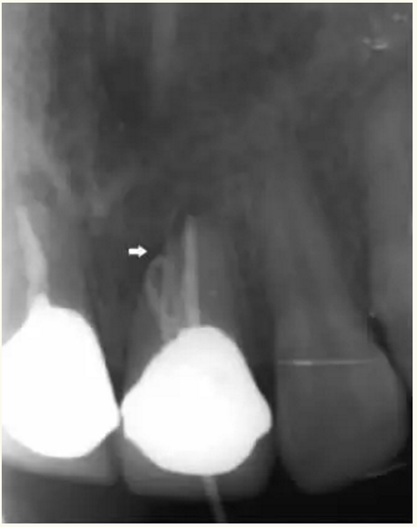

▲術(shù)后,手術(shù)切口處疤痕

▲術(shù)后,X線顯示:21根尖切除區(qū)域骨質(zhì)修復(fù),根管倒充填物完好,原牙周膜間隙增寬影消失